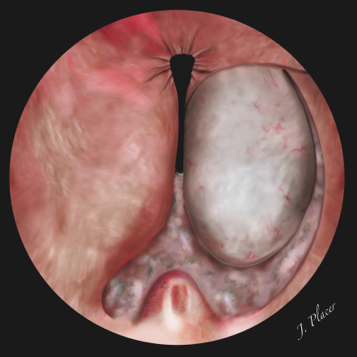

La disección del extremo caudal del lóbulo apical izquierdo debe continuarse en sentido contrario a las agujas del reloj desde la línea media hasta las 1-2 horarias. El objetivo es liberar el lóbulo apical de la cápsula prostática todo lo que sea posible. Durante su realización hay que controlar periódicamente la posición del esfínter externo y evitar el deslizamiento caudal con respecto al verumontanum del resectoscopio. Tras su realización, el restante lóbulo lateral izquierdo es enucleado de forma retrógrada desde el lóbulo apical hasta el borde del cuello vesical (Figura 7). La enucleación del lóbulo lateral se logra por la combinación del corte y coagulación del láser y la disección ejercida a modo de palanca por el propio resectoscopio. La incisión realizada a las 5, 6 o 7 horarias, según la estrategia empleada inicialmente, permite identificar el plano de la cápsula y seguirlo. Una vez que se ha alcanzado el plano de disección el lóbulo lateral suele despegarse con suma facilidad de la cápsula. De gran utilidad es invertir el endoscopio para que la propia vaina interna del resectoscopio levante el adenoma y ayude a despegarlo de la cápsula. En ocasiones se tiene dificultad para levantar y disecar el lóbulo lateral porque el lóbulo apical izquierdo permanece todavía fijo en algún punto a la cápsula de la próstata. Por este motivo solemos demorar la disección del lóbulo lateral hasta que la mayoría del lóbulo apical está liberado. Varios fabricantes han desarrollado elementos de trabajo que además de tener un canal por el que se introduce la fibra del láser disponen de una o dos asas metálicas en su extremo distal. El empleo de estos elementos de trabajo puede facilitar la enucleación ya que ayudan a levantar el adenoma y despegarlo de la cápsula prostática.

Figura 7. Disección del lóbulo lateral izquierdo